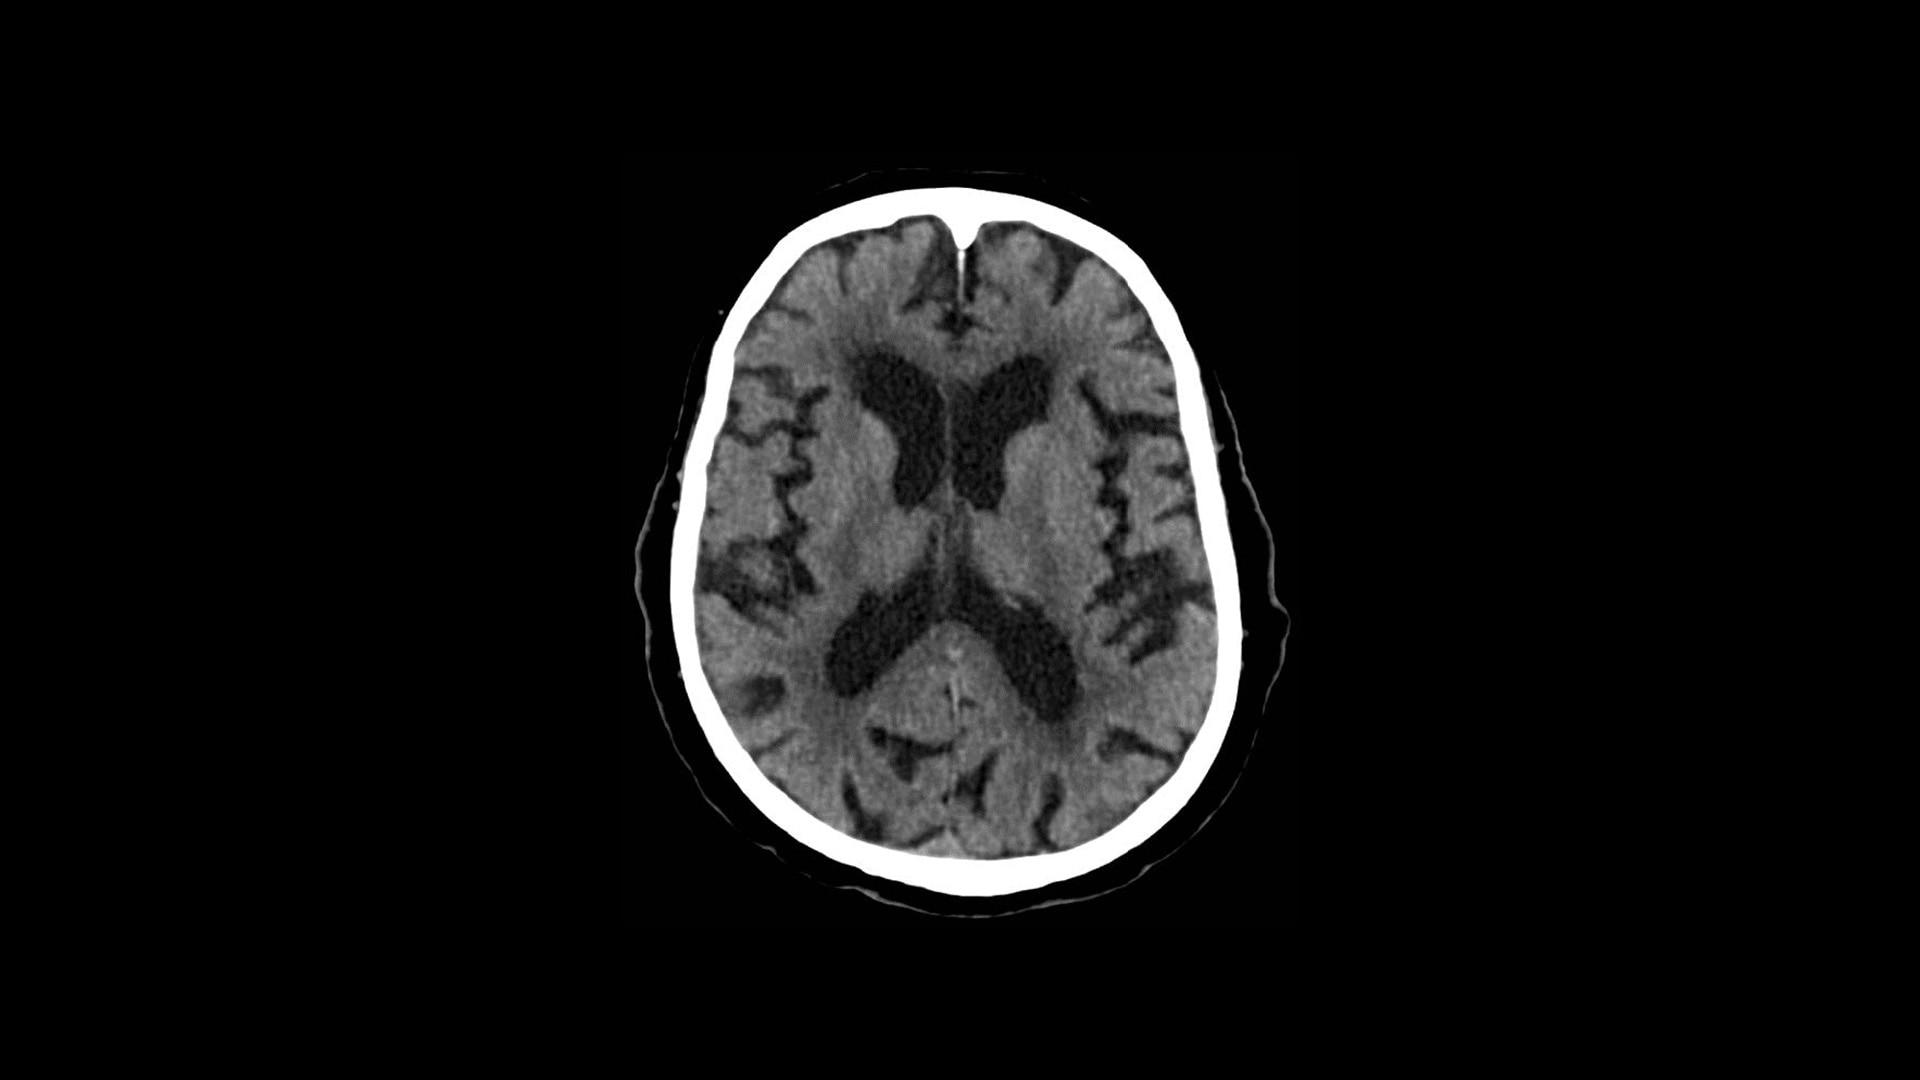

TrueFidelity DL

Deep learning for a deeper understanding

TrueFidelity™ DL is our state-of-the-art image reconstruction technology that uses a DNN to generate high-definition, low-noise CT images. It produces images with exceptional sharpness, low-contrast image quality performance and your preferred noise texture, at the same dose.¹